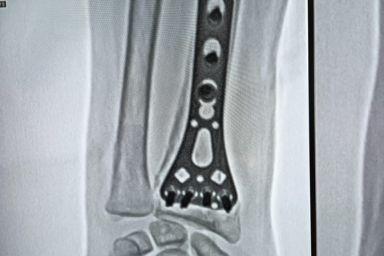

Advanced Orthopaedic Care with Modern OT Facilities by Dr S R Panda

Dr S R Panda is a reputed orthopaedic surgeon in Kolkata offering advanced facilities including General & Joint Replacement OT, Arthroscopy & Trauma OT, and Spine Surgery & Sports Injury OT, ensuring precise diagnosis, modern surgical techniques, and comprehensive bone and joint care under one roof.

General & Joint Replacement OT